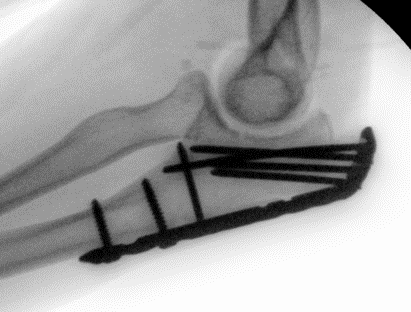

Tension band wire

Indication

Fracture proximal to center of rotation / midpoint of trochlea

Convert tensile distraction force of triceps into a compressive force

Issue

High rate of metal prominence / need for removal

Contra-indication

Fracture distal to center of rotation

Highly comminuted fractures

Oblique fractures

Technique

- fix with unicortical K wires

- drill hole in ulna distally

- pass 20 gauge wire and form figure of 8 wire about wires, can pass under triceps

- twist via 2 knots